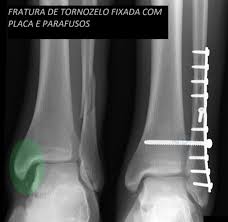

3.Fixação de fraturas (Osteossíntese)

É a cirurgia para alinhar e estabilizar fraturas ósseas com o uso de:

• Placas e parafusos

• Pinos e hastes intramedulares

• Fixadores externos

Indicada em fraturas com desvio, exposição ou que não ciclam adequadamente com gesso.